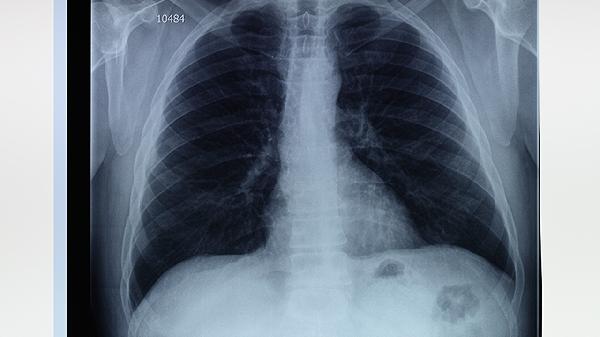

怎样治疗肺大泡

肺大泡的治疗方法包括药物治疗、手术治疗和生活方式调整,具体选择取决于病情严重程度和患者整体健康状况。肺大泡是由于肺泡壁破裂融合形成的囊状结构,常见于慢性阻塞性肺疾病COPD、肺气肿等疾病,需及时干预以避免并发症。